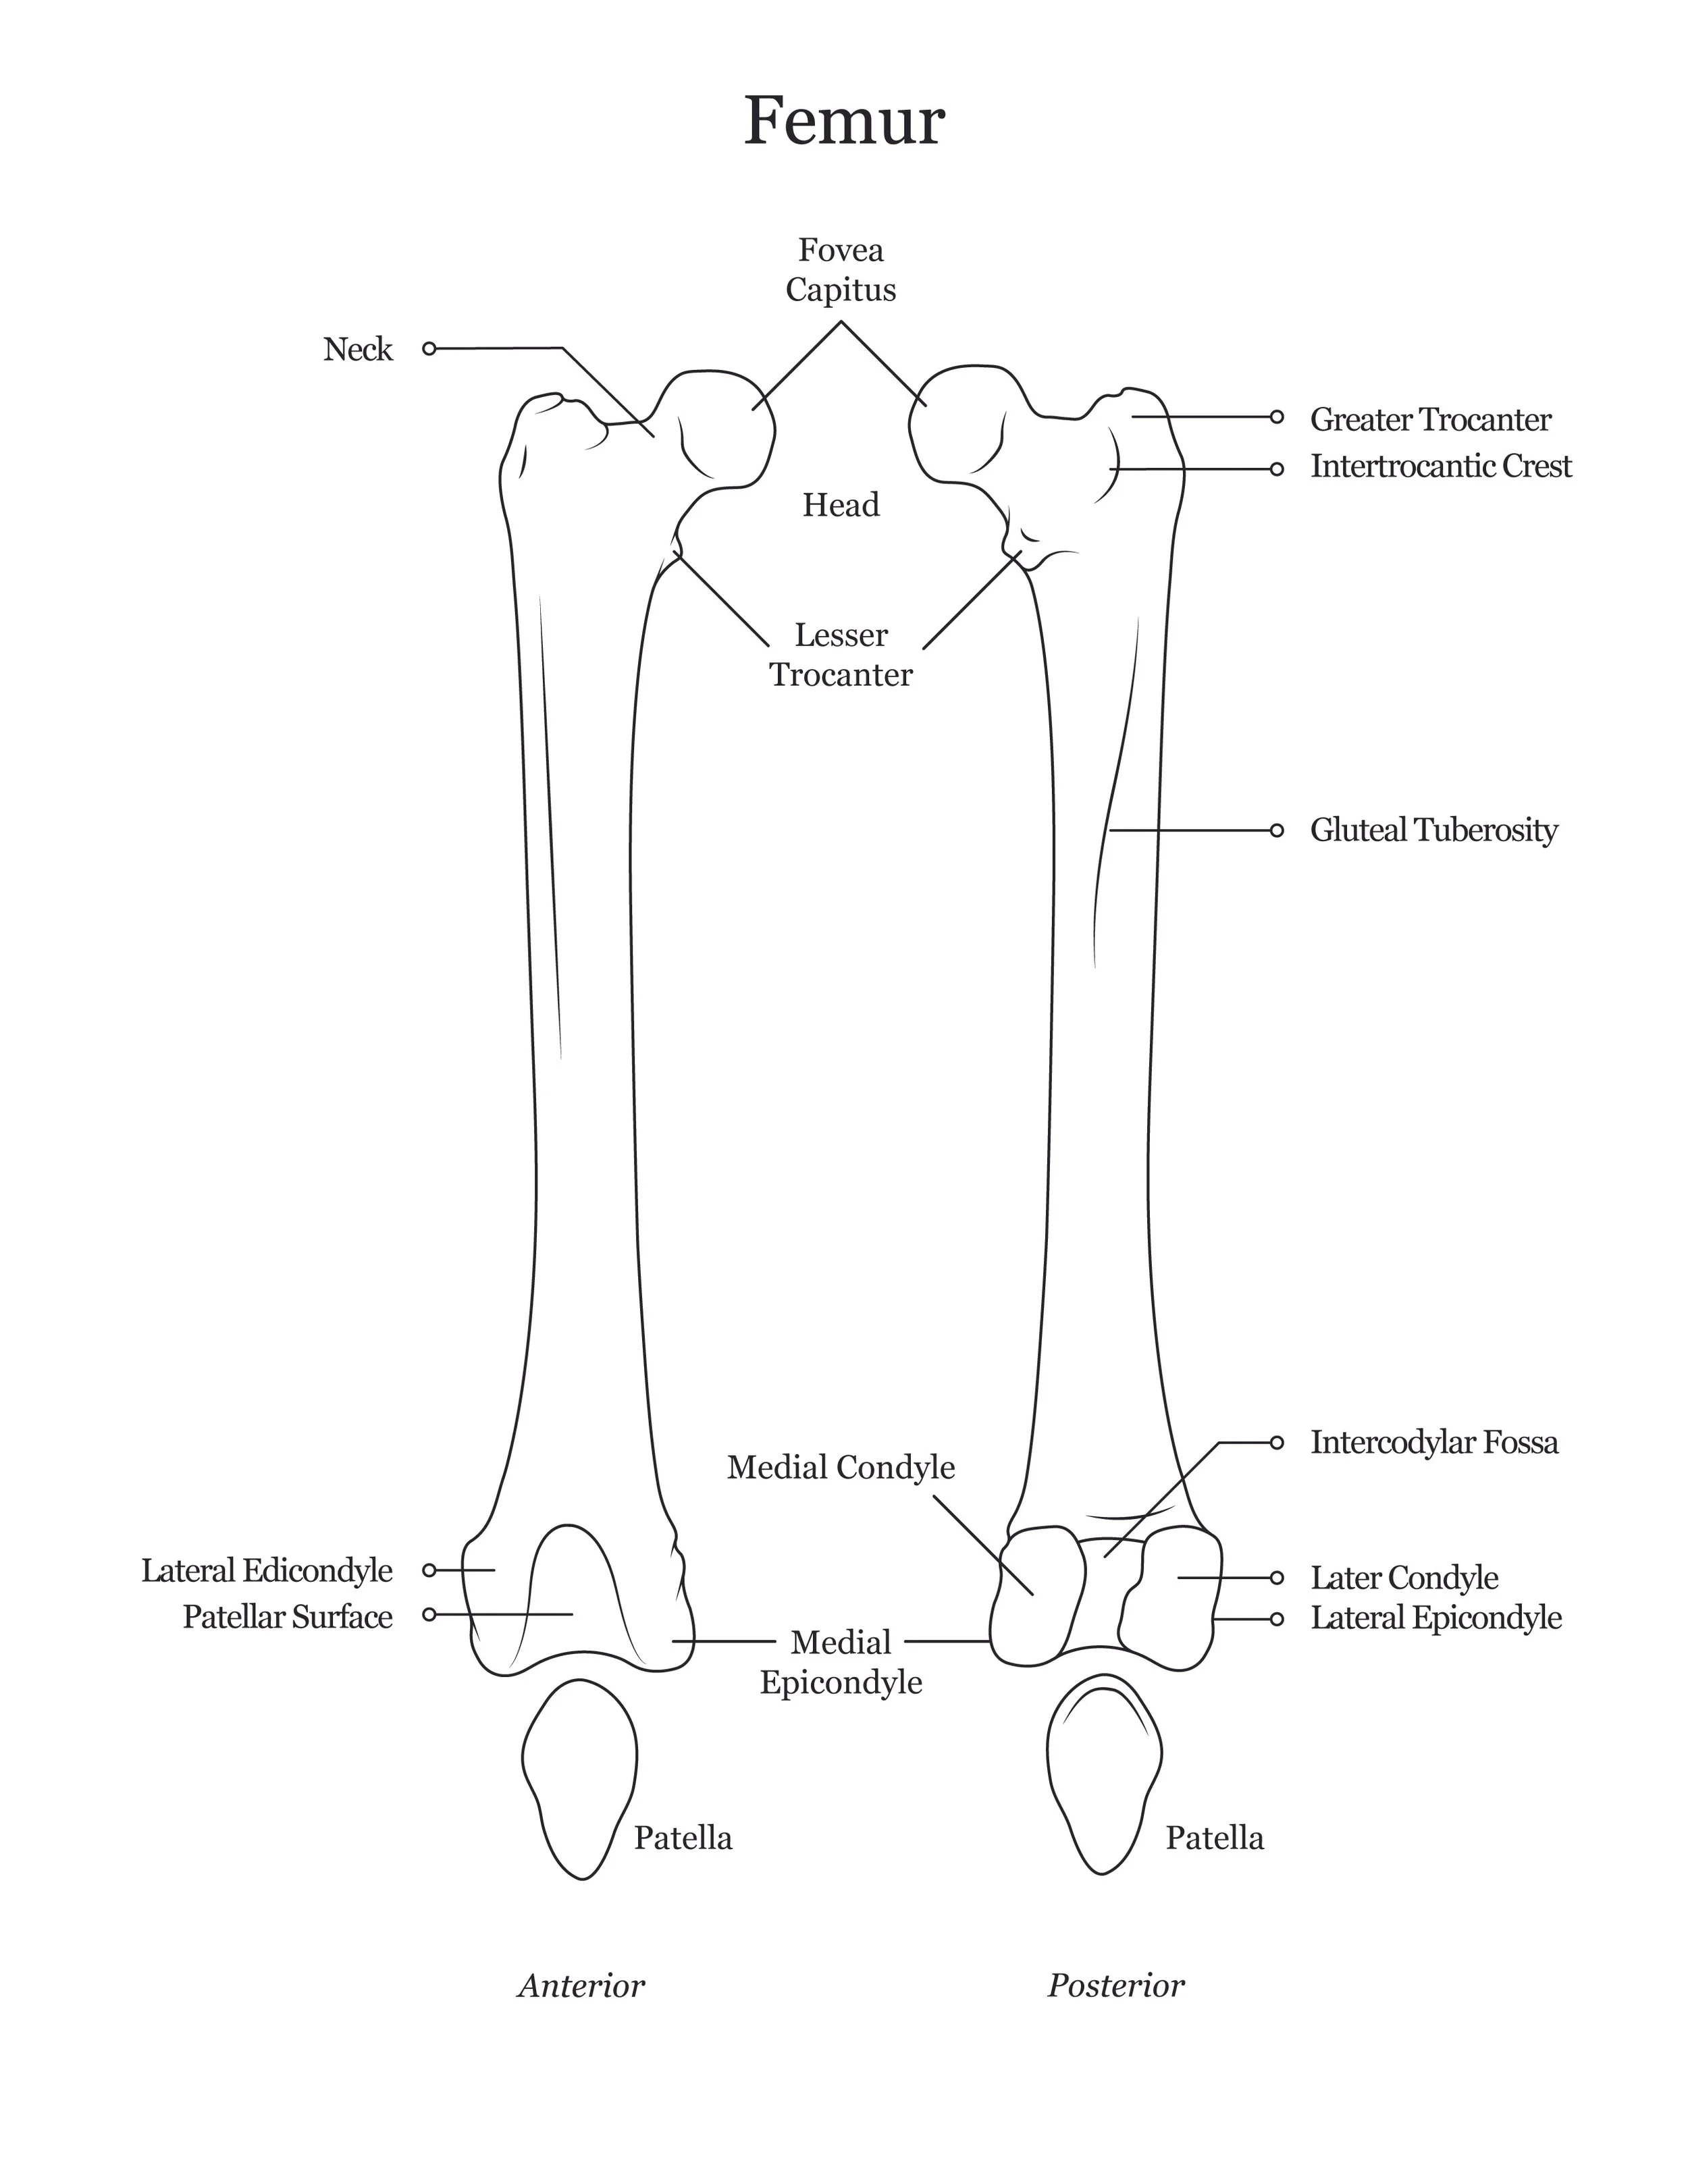

A series of anatomical illustrations created for Arcadia University’s Biology Department.

This project involved illustrating a series of diagrams for a cat dissection manual, focusing on skeletal and muscular anatomy. I consolidated multiple reference sources and firsthand specimen observation into a cohesive visual system for instructional use. Illustrations were refined iteratively to ensure anatomical accuracy, consistency, and clarity for students.